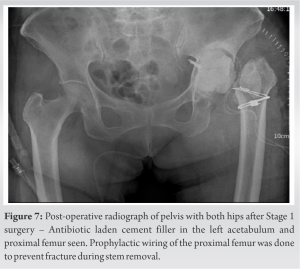

Once the adhesions were released, the external iliac vessels were protected with saline-soaked gauze, the incision was temporarily closed and the patient was carefully repositioned from supine to lateral decubitus position. The hip joint was exposed through the posterior approach. After removal of the femoral component and the acetabular polyethylene liner, the screws were gently removed to explant the acetabular shell. The broken screw was completely embedded in the pelvic bone and could not be removed. We decided to leave it behind as it was not abutting any important structure. Intraoperative frozen section was not available at our hospital and therefore tissue samples were collected and sent for bacterial cultures. Antibiotic-laden polymethylmethacrylate cement containing 80mg Gentamicin and 2g Vancomycin was used to fill the acetabular cavity and proximal femoral canal (Fig. 7). Incision was closed, keeping a negative suction drain. The integrity of the external iliac vessels was reconfirmed (Fig. 8) and then the anterior incision was finally closed. Postoperatively, the patient was observed closely for any signs of internal bleeding and delayed injury to vessels. Infection assessment with parameters such as TLC, ESR, CRP levels, and daily drain output was done. Intraoperative samples for bacterial cultures turned out to be inconclusive, showing no bacterial growth after 2 weeks of incubation period. Definitive surgery was then scheduled and during this surgery, the cement filler was extracted and the acetabular bone defect was reconstructed using trabecular metal augment in a flying buttress mode [5]. Impaction bone grafting using morselized allograft was done to build up the medial acetabular floor and a multi-hole uncemented acetabular shell was implanted. Acetabular screws were placed carefully according to the maximum bone available for fixation, the screw lengths were determined using the pre-operative CT scan. Screw insertion in the posterosuperior zone was not feasible due to the trabecular metal augment. A long hydroxyapatite-coated femoral stem was press-fitted. Post-operative radiograph shows correction of the limb length discrepancy (Fig. 9). In bed and bedside rehabilitation was started on the same evening. Toe-touch weight bearing, giving 20–30% of body weight was started on the third post-operative day with the help of a walker and full weight bearing was gradually allowed after 6 weeks